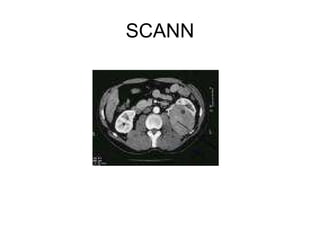

scanner

SCANN